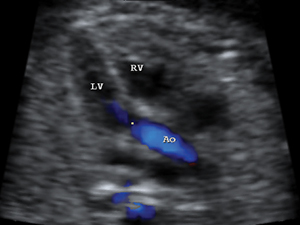

心臟

胎兒心臟主動脈外流道平面圖

心臟主動脈外流道以彩色顯示血流方向